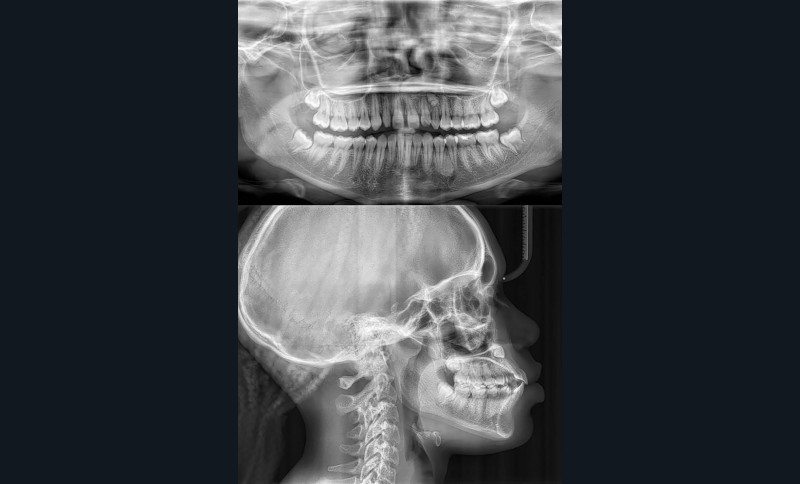

La radiographie panoramique permet de confirmer l’inclusion de la 23, apicale aux dents 21 et 22, ainsi que la présence d’un odontome en apical de la 63. Ces éléments nécessitent la réalisation d’un CBCT.

Le CBCT révèle une position très apicale de la 23. L’apex est fermé.

La téléradiographie de profil montre une Classe II squelettique par biprognathie, avec proalvéolie et vestibuloversion de l’incisive mandibulaire.